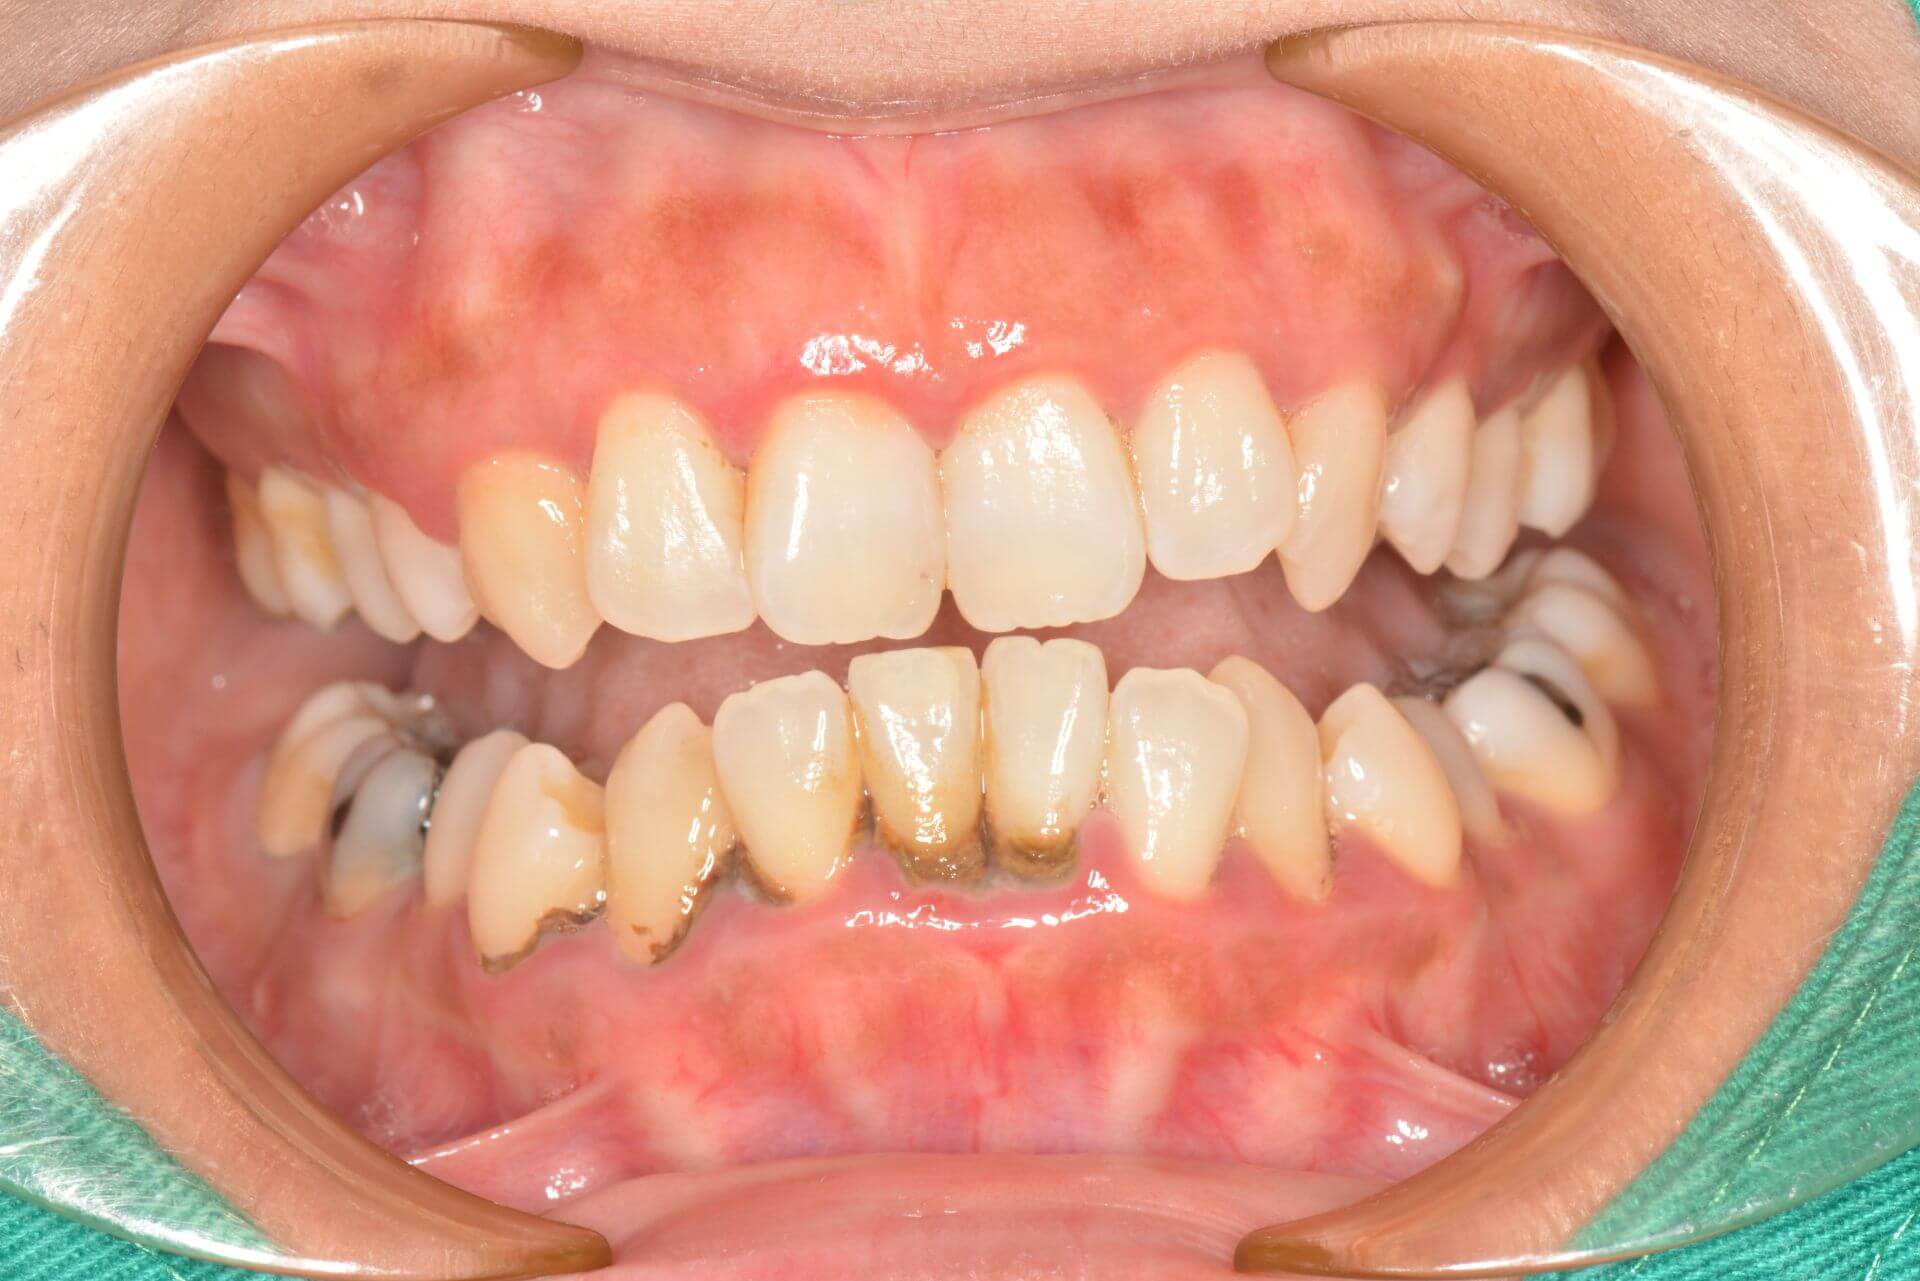

案例